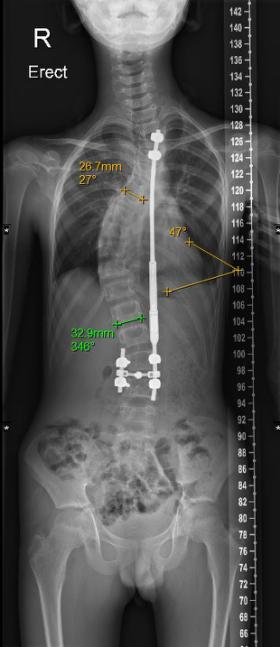

小磊手术前评估(左图),Cobb角度为61度,术后(右图)约为30度

在张文智教授团队及多学科共同合作下,小磊于5月3日进行了手术,手术时长约3小时,Cobb角由术前61度矫正为30度,手术进行得非常成功,“后续小磊只需要每2-3个月定期复诊一次即可。预计在植入的1-2个月后可撑开钛棒,并在未来三年内定期通过仪器进行体外拉伸,调整钛棒长度及脊柱角度,直到基本痊愈。”